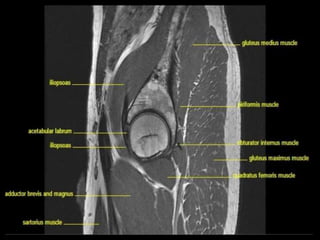

Hip Joint.